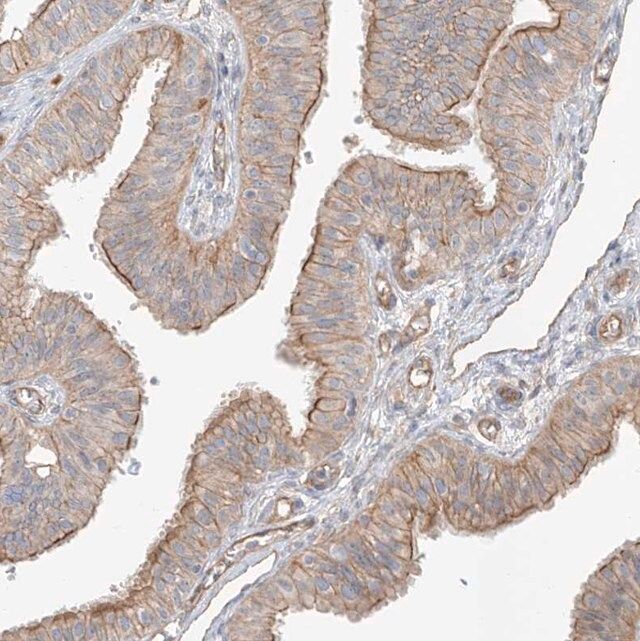

| Application【应用】 | All Prestige Antibodies Powered by Atlas Antibodies are developed and validated by the Human Protein Atlas (HPA) project (www.proteinatlas.org)and as a result, are supported by the most extensive characterization in the industry. The Human Protein Atlas project can be subdivided into three efforts: Human Tissue Atlas, Cancer Atlas, and Human Cell Atlas. The antibodies that have been generated in support of the Tissue and Cancer Atlas projects have been tested by immunohistochemistry against hundreds of normal and disease tissues and through the recent efforts of the Human Cell Atlas project, many have been characterized by immunofluorescence to map the human proteome not only at the tissue level but now at the subcellular level. These images and the collection of this vast data set can be viewed on the Human Protein Atlas (HPA) site by clicking on the Image Gallery link. To view these protocols and other useful information about Prestige Antibodies and the HPA, visit sigma.com/prestige. |

| technique(s) | immunofluorescence: 0.25-2 μg/mL immunohistochemistry: 1:50-1:200 |